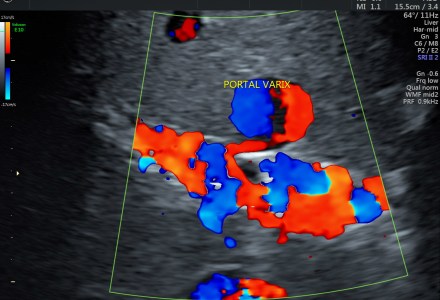

VASCULAR MALFORMATION IN THE LIVER